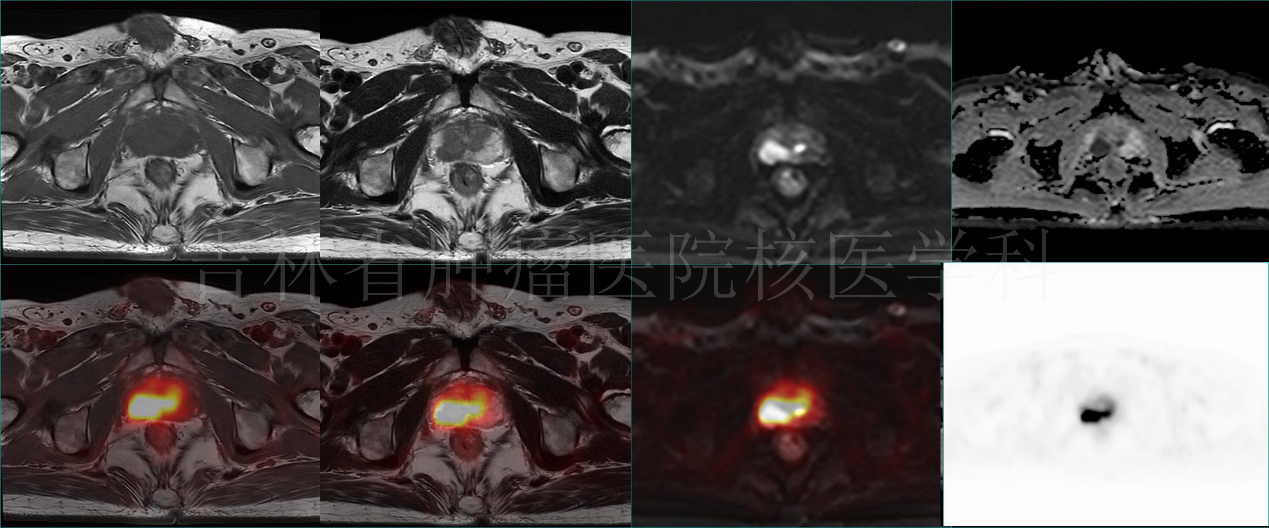

病例3 PET/MR診斷前列腺癌:前列腺右側(cè)外周帶結(jié)節(jié),T1WI呈等信號,T2W呈稍高信號,DWI呈高信號,ADC值減低,伴18F-FDG攝取增高(病理結(jié)果:前列腺癌)